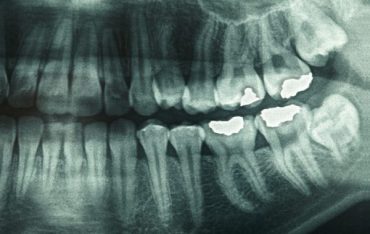

Ingeniously Simple Dental Treatment Could Heal Tooth Cavities Without Any Fillings

Ingeniously Simple Dental Treatment Could Heal Tooth Cavities Without Any Fillings Scientists have invented a product that can encourage tooth … Continue reading Ingeniously Simple Dental Treatment Could Heal Tooth Cavities Without Any Fillings